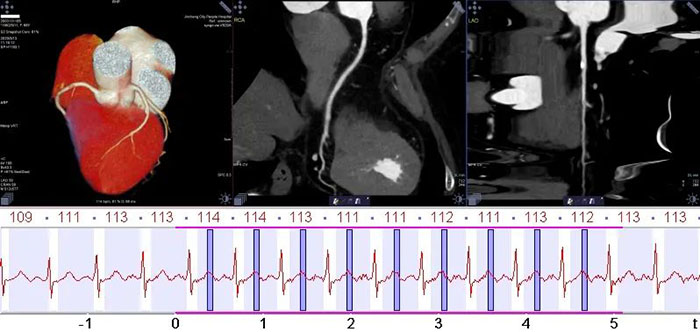

冠状动脉CTA检查心率不受限

双64排探测器,0.25秒超高转速,时间分辨率达75ms,冻结心跳,实现无禁忌冠状动脉成像。

因为扫描速度快,可以在一次心跳内完成心脏扫描,对于心率不齐,心跳过快的病人可以在不用药物限制心率的情况下,直接做冠脉CT检查,免去了控制心率的等待时间。